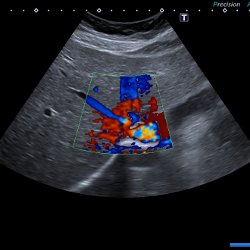

Ultraschall